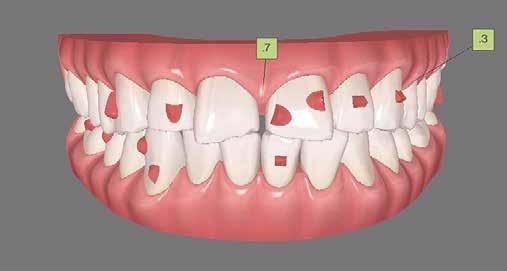

A 26 éves férfi páciens azzal a kéréssel kereste fel a rendelőnket, hogy a frontfogai esztétikusabb megjelenését szeretné elérni. A páciens jó általános egészségi állapottal rendelkezett, nem szenvedett allergiáktól és nem kellett rendszeresen gyógyszereket szednie. A páciens lehetőség szerint kerülte a fogai megmutatását. Rendkívül zavarónak találta a nagymetszői között, a középvonalnak megfelelően látható rést, a fogain látható kopási jeleket, valamint a fogai méretét is túl kicsinek találta. A szájüregi vizsgálat során megállapítottuk, hogy a nagymetsző fogai (11, 21) élharapásban vannak, valamint az alsó fogíven kismértékű torlódást észleltünk. A felső frontfogakon

(13-23) attrícióra utaló jeleket találtunk. A fogak kopása a nagymetszőfogaknak megfelelően volt a legkifejezettebb (1. ábra) . Az előbbiekben említett fogak (11, 21) ezen kívül némileg elfordultak, és jelentősebb méretű diasztéma volt köztük. A páciens Angle I.-osztályú állcsontrelációs helyzettel rendelkezett. A vizsgálat során feltűnt, hogy a páciens csak nagyon óvatosan mert mosolyogni (2. ábra)

A szájüregi vizsgálat során nem találtunk szuvas léziók jelenlétére utaló eltéréseket. A nagymetszőfogakon megfigyelhető jelentős mértékű kopás ellenére nem észleltünk craniomandibuláris diszfunkció jelenlétére utaló jeleket. A vizsgálat befejezését követően a pácienst tájékoztattuk a különböző kezelési lehetőségekről. Az esztétikai megjelenés javítása érdekében először egy alignerekkel végzett fogszabályzó kezelés elvégzését, majd a harapási helyzet optimalizálását követően a felső frontfogai kompozittal történő direkt felépítését vagy héjakkal történő ellátását (pl.: non-prep héjak) javasoltuk (3. és 4. ábra).

A fogazat minimálinvazív módon készített héjakkal történő ellátásához a fogaknak olyan pozícióban kell lenniük, amely lehetővé teszi az esztétikai megjelenés additív eljárások alkalmazása mellett történő optimalizálását.1. ábra: Kiindulási állapot. A felső nagymetszőfogak élharapásban vannak. 2. ábra: Az orthodonciai kezelés megkezdése előtt készített intraorális felvétel. A páciens csak óvatosan mer mosolyogni. 3. és 4. ábra: Digitálisan megtervezett kezelés.

A kezelések második fázisában a pácienssel közösen non-prep/ minimálinvazív héjak készítése mellett döntöttünk (6. és 7. ábra).